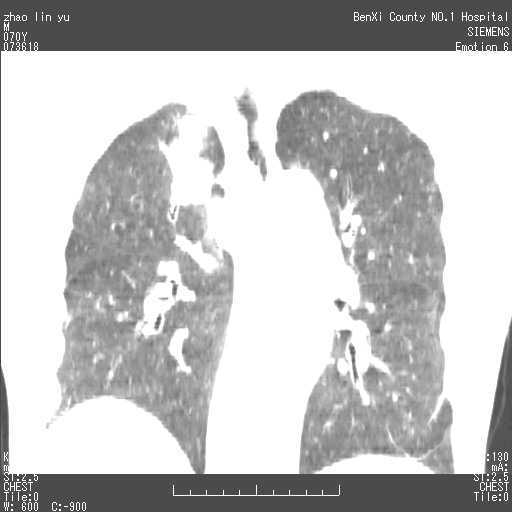

以下是引用王靖旗在2007-7-10 17:12:00的发言:[br] 男、70、咳嗽两个月,半年前换瓣手术,胸片未见异常,于昨天行x片发现右肺上野大片影,行ct扫描,这里是减薄图像,余肺正常。明天晚上会有增强扫描片,到时我会上传。[br][br] 冠状位请大家细看,应该是有意义的,[br][br] 请大家先看平扫发表意见。[br][br]

[br]冠状面[br]

以下是引用zhangzhongshou在2007-7-10 21:43:00的发言:[br]右肺上叶周围型肺癌,以孤立型细支气管肺泡癌可能性大。